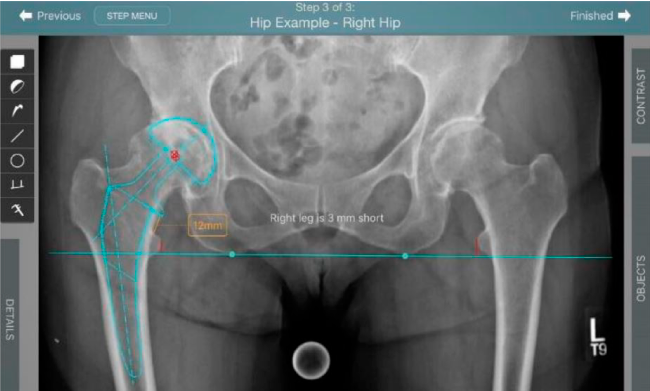

Anotaciones digitales y herramientas de análisis de longitud de pierna.

Con tecnología ONETRIAL® que calcula automáticamente el cambio en la longitud de la pierna y el desplazamiento para todas las combinaciones de implantes en una tabla fácil de leer.